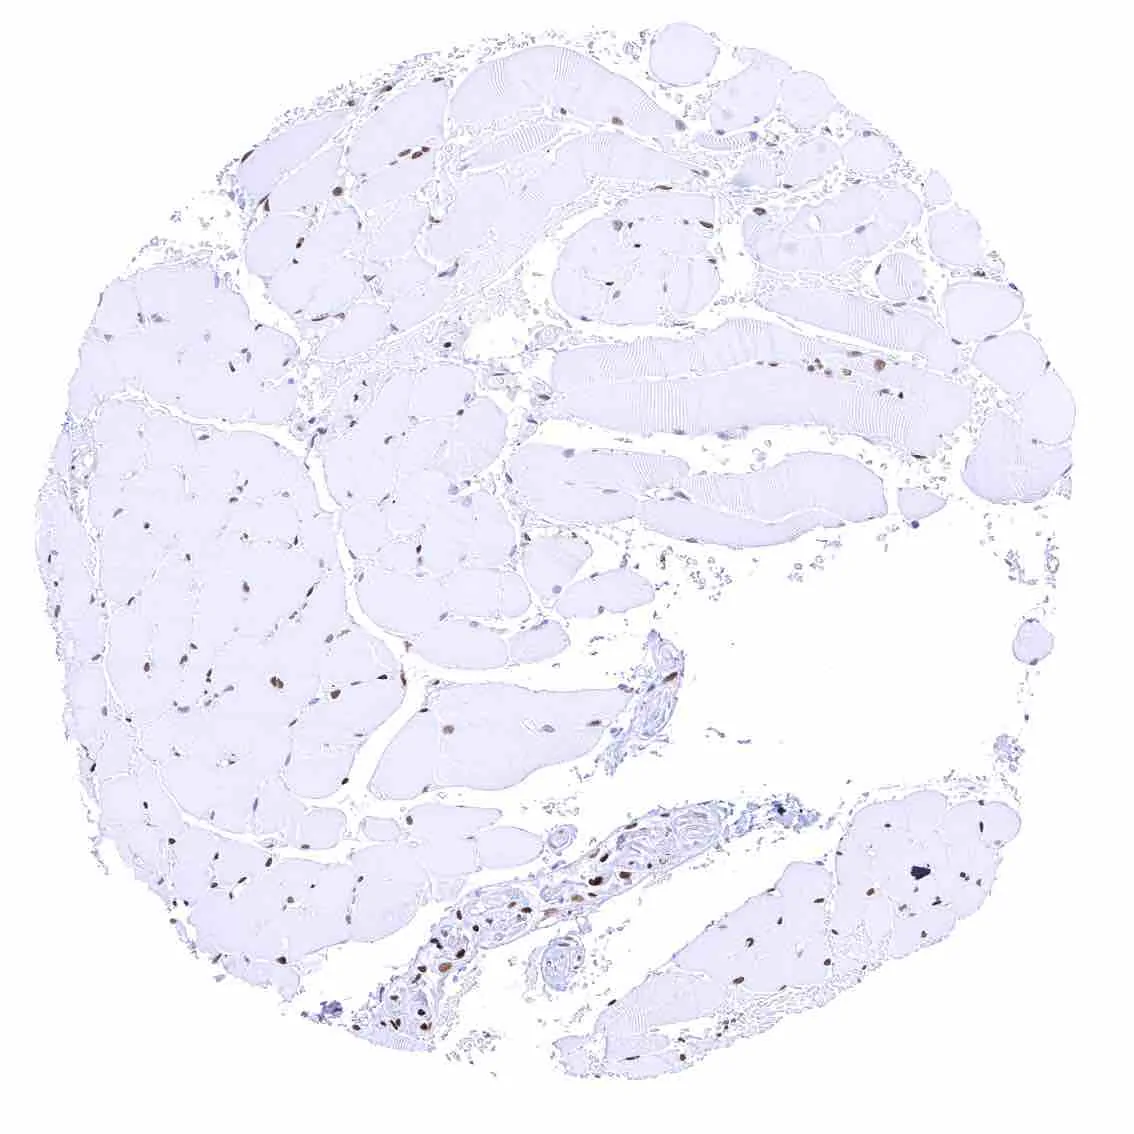

Adrenal gland – Distinct nuclear p27 positivity of a large fraction of cells.